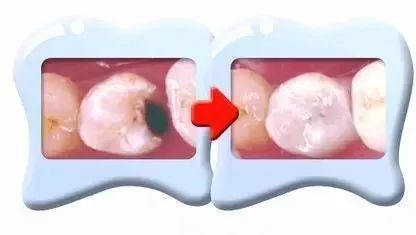

第一個階段:牙齒面上有條黑線,大牙最常見,係話,牙釉質俾細菌蛀壞,不過無痛無癢,要快啲補牙;

第二個階段:牙齒出現小黑洞,係話,細菌蝕牙到牙本質,仲有牙齒敏感,黑色腐敗嘢係細菌嘅產物,而家仲可以補牙;

複合樹脂,近牙色嘅填補材料,黐合力唔錯,特別耐磨又抗蝕,補牙後都睇唔到有痕跡,大人同細路都適用。